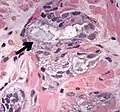

Intraductal carcinoma of the prostate with an infiltrative growth pattern may be morphologically difficult to distinguish from invasive cancer. One focus shows comedonecrosis (arrow), morphologically suggesting Gleason pattern 5 invasive carcinoma (a haematoxylin and eosin, b CK5/6)[20] -

Intraductal carcinoma of the prostate with very patchy basal cells identified by immunohistochemistry. At least some of the glands lacking basal cell immunoreactivity represent intraductal rather than invasive carcinoma (a haematoxylin and eosin, b CK 5/6)[20]